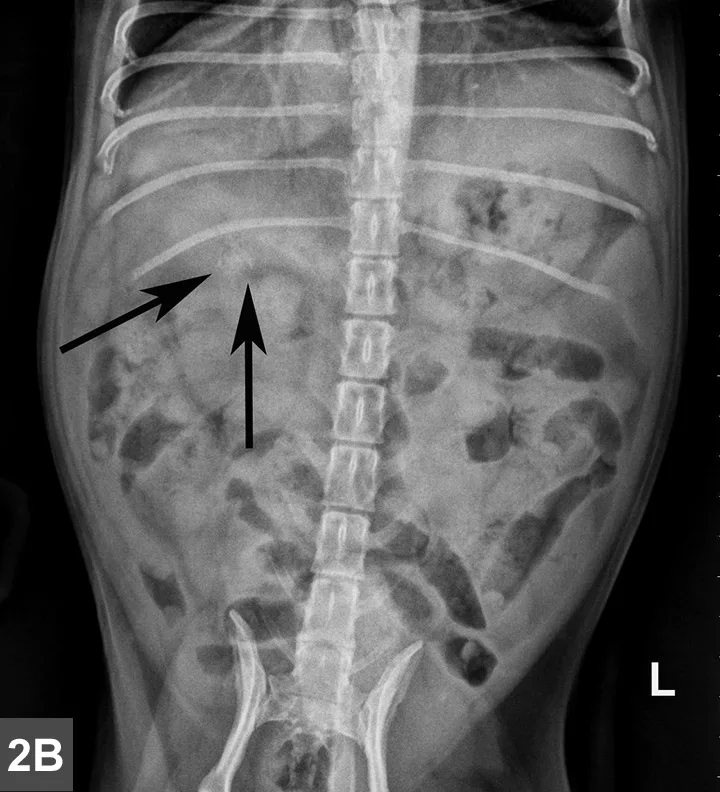

Left lateral (Figure 1A) and VD (Figure 1B) radiographs of the abdomen were obtained. Although thoracic radiographs were also taken, the findings were considered normal and, therefore, are not included here.

Figure 1A & B

Left lateral (Figure 1A) and VD (Figure 1B) views of the abdomen.

Radiographic Findings

A mottled mineral opacity measuring ~12 mm in diameter is seen just caudal to the last right rib in the VD view, near the pyloroduodenal junction (Figure 2B, black arrows), and superimposed over the pylorus in the lateral view (Figure 2A, black arrows). This opacity could be a foreign body or a mineralized mass or lymph node. Heterogeneous soft tissue material, compatible with ingesta, is present in the gastric lumen as well as throughout the intestines, but no abnormal distention is evident. The liver extends past the costal arch with mild caudal displacement of the gastric axis, consistent with mild hepatomegaly; the margins are smooth. The remaining viscera and serosal detail are normal.

Figure 2A & B

Same lateral and VD radiographs as in Figure 1A and B showing mineral density just caudal to the last right rib in the VD view (Figure 2B, black arrows) near the pyloroduodenal junction and in the lateral view (Figure 2A, black arrows) superimposed over the pylorus.